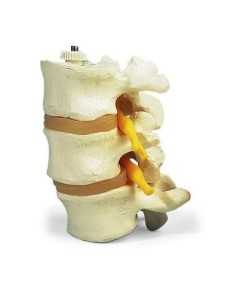

Colonne lombaire 3B Scientifique avec hernie discale dorsolatérale A76/5

Des modèles anatomiques détaillés pour tous les besoins

Du crâne en 22 parties à verrouillage magnétique aux modèles de colonne vertébrale, des modèles d'articulation aux modèles de cœur, chaque pièce de notre collection est conçue pour une immersion totale dans l'étude de l'anatomie humaine. Nos modèles, réalisés à partir de scans d'os réels, garantissent une expérience tactile authentique et une fidélité de poids presque identique aux originaux.

Indispensables aux étudiants comme aux professionnels, nos modèles anatomiques sont des outils pédagogiques qui permettent d'observer les structures anatomiques avec précision, en évitant les dissections ou les études invasives. Ils sont également utiles pour expliquer les pathologies aux patients, ce qui rend la communication plus efficace et permet de gagner un temps précieux.